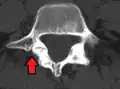

| Spondylolisthesis | |

| |

| X-ray of the lateral lumbar spine with a grade III anterolisthesis at the L5-S1 level | |